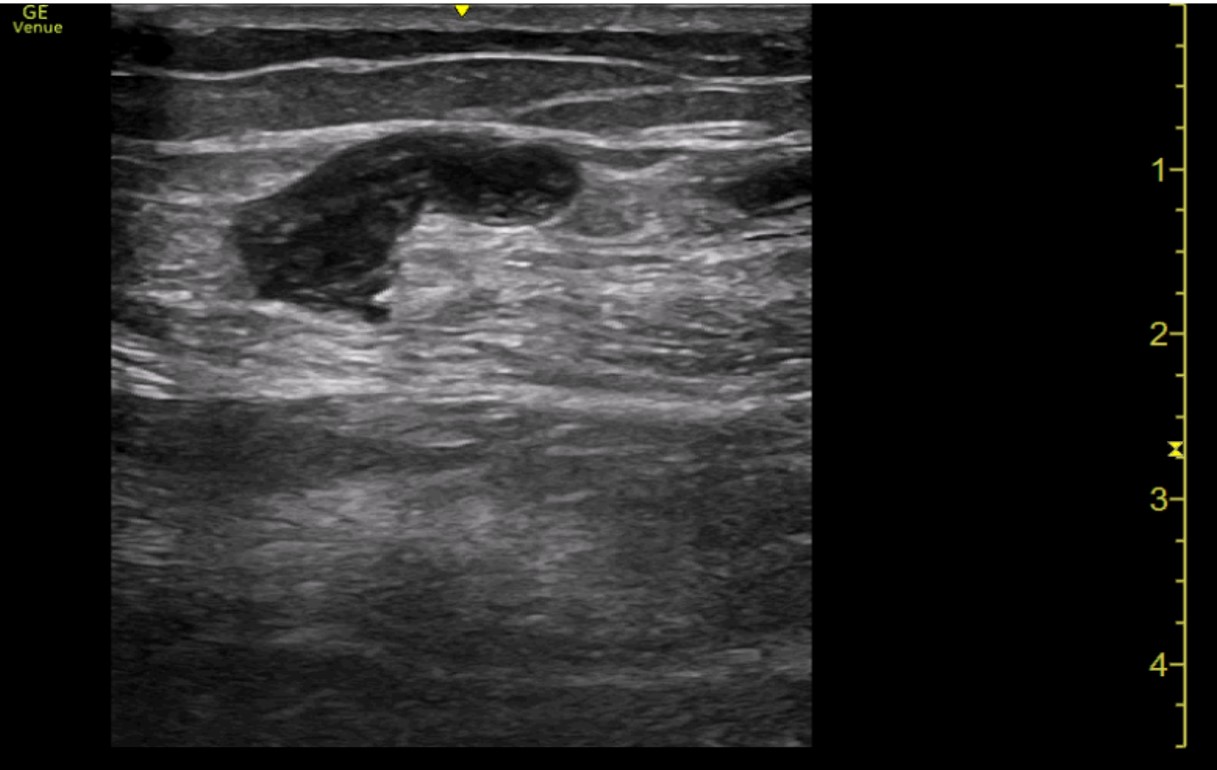

Ecografía a pie de cama: Con sonda lineal, se comienza visualizando vena femoral profunda, la unión de vena safena mayor y la vena poplítea, todas ambas con buena compresión. Por último, se visualiza región dolorosa del paciente, donde se observa vena superficial con contenido hiperecogénico en su interior y ausencia de cambios con la compresión. Se delimita dicha región con longitud inferior a 5 cm y a más de 5 cm de unión safeno-poplítea.

Trombosis venosa superficial.

En consultas, mejoría clínica y ecográfica de la trombosis. Sin complicaciones posteriores.